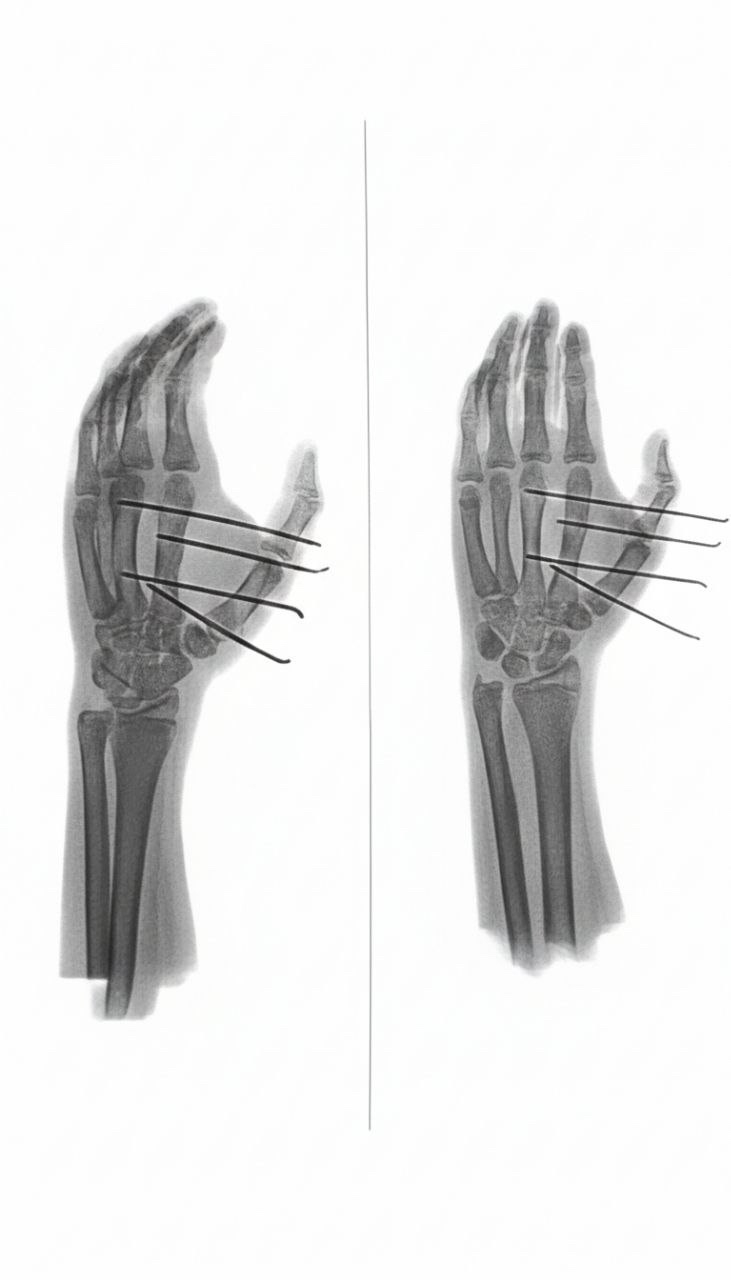

В отделении травматологии ОДКБ проведена уникальная технически сложная операция юному пациенту, пострадавшему от взрыва пиротехнического устройства. 13-летний подросток получил тяжёлое ранение руки минно-взрывной травмой и инородным телом второй пястной кости.

С помощью современного метода мягкого внешнего остеосинтеза посредством фиксации костных фрагментов специальными спицами, зафиксированными между собой, врачам отделения удалось восстановить анатомическую целостность кости и прилегающих мягких тканей – раздробленную взорвавшейся петардой кисть собрали практически заново.